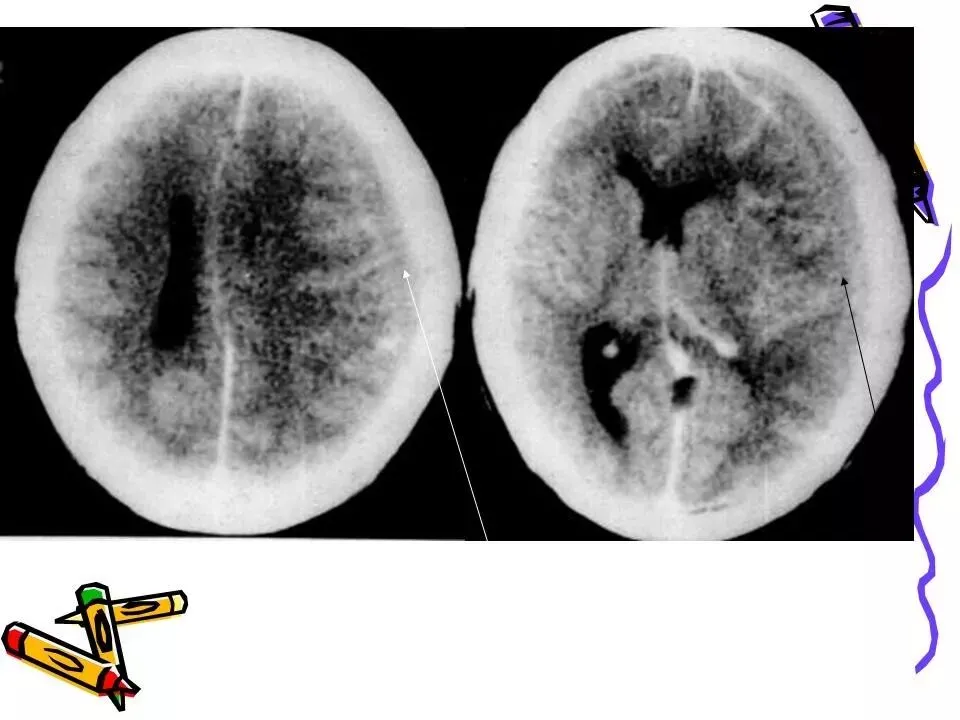

>常见颅脑外伤CT诊断(PPT)

常见颅脑外伤CT诊断(PPT)